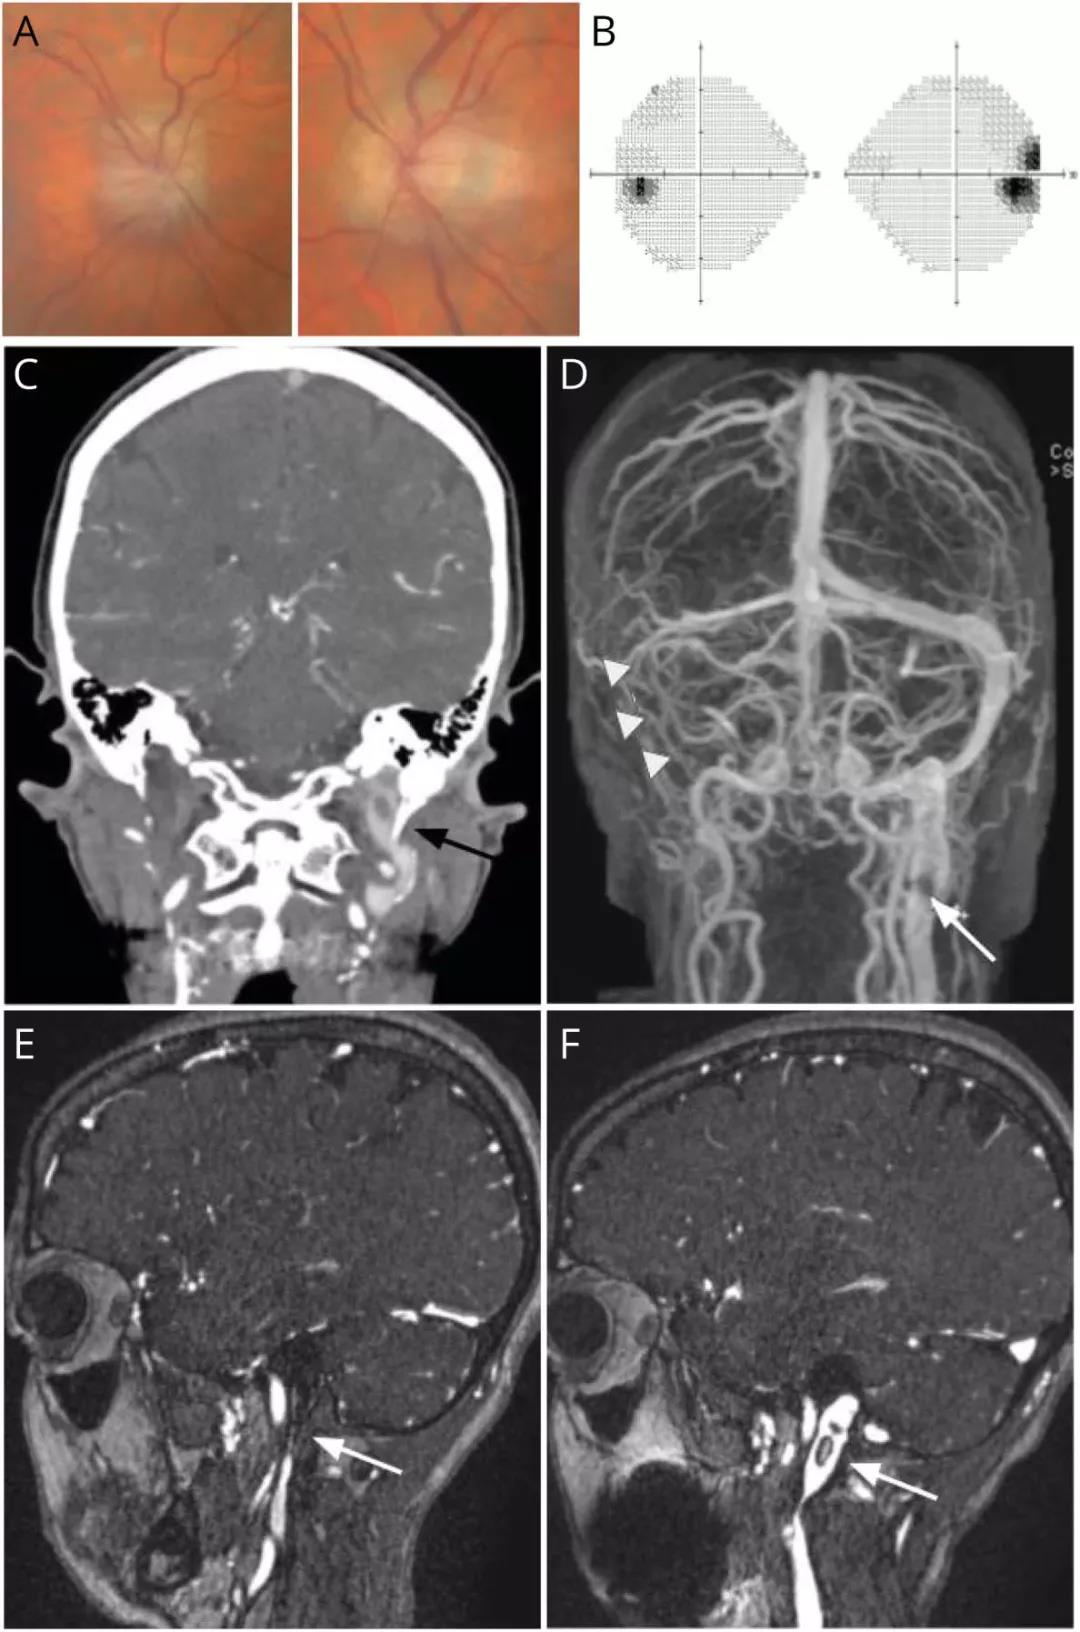

65岁,女性。

头痛,搏动性耳鸣和视物模糊。

(A)眼底照片显示双侧视盘水肿。(B)Humphrey视野(24-2算法)显示右眼盲点扩大。(C)头部冠状位增强CT显示茎突过长压迫左颈内静脉(黑色箭头)。(D)MRV冠状位显示右横窦远端、乙状窦和颈内静脉未显影(白色箭头),左颈内静脉内血栓导致充盈缺损(白色箭头)。(E)矢状位MRV图像几乎看不见的右颈内静脉(白色箭头)(作者认为血栓形成,译者觉得不除外发育的问题)。(F)矢状位MRV图像显示左颈内静脉内有薄的非闭塞性血栓形成(白色箭头):

易栓症相关筛查发现血栓前JAK2 V617F突变。JAK2 V617F替代(substitution)是骨髓增生性肿瘤的驱动突变,几乎在所有真性红细胞增多症(PV)病例和50%-60%的原发性骨髓纤维化和原发性血小板增多症病例中都存在。

最终该患者诊断为静脉窦血栓形成,主要原因为JAK2 V617F突变,茎突过长压迫左颈内静脉诱发了血栓形成。